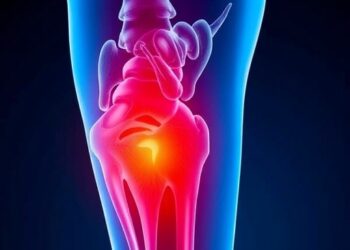

Evaluating Social Media on Femoral Head Necrosis

In the age of digital information, social media has emerged as an influential platform for health communication, shaping public understanding...